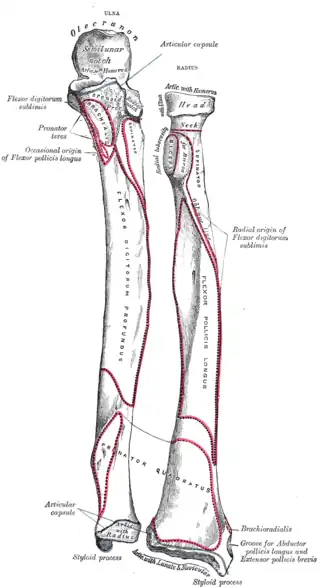

Le muscle biceps brachial se termine par un tendon plat qui s’insère sur la partie postérieure de la tubérosité du radius.

Le tendon libère des expansions aponévrotiques qui recouvrent le fascia antébrachial médial [2], sur la face latérale du radius. Il forme également une expansion de l'aponévrose du muscle (lacertus fibrosus) qui cravate les tendons des muscles épicondyliens médiaux s'achevant sur l'ulna.

Il peut exister de façon inconstante une bourse cubitale interosseuse qui sépare le tendon de la corde oblique ou de l'ulna.

Origine du chef long du muscle biceps brachial Insertion radiale du muscle biceps brachial

Insertion radiale du muscle biceps brachial